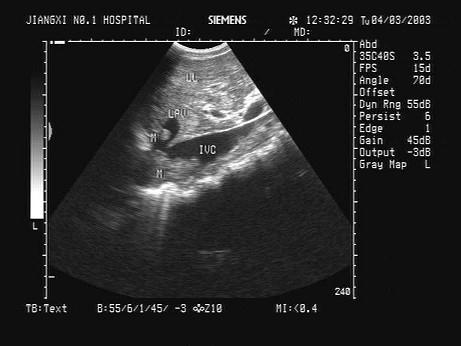

问题 某患者肝脏及下腔静脉肝段内见异常回声。声像图表现如图,诊断为?(?)

选项 A.艾森曼格综合征 B.布加综合征 C.麦格综合征 D.川畸病 E.马方综合征

答案 B